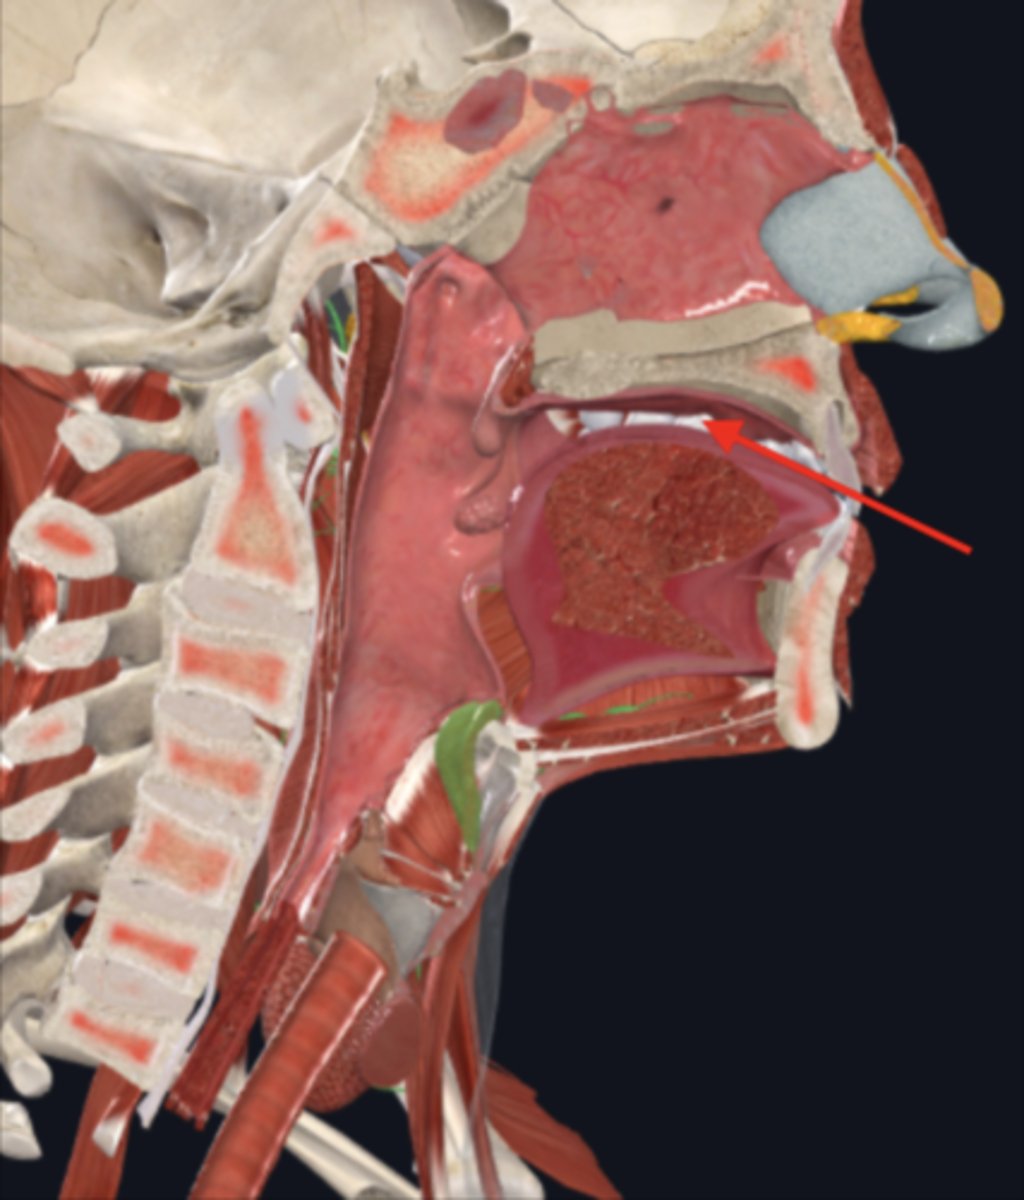

nasopharynx

name the circled region

oropharynx

name the circled region

laryngopharynx

name the circled region

epiglottis